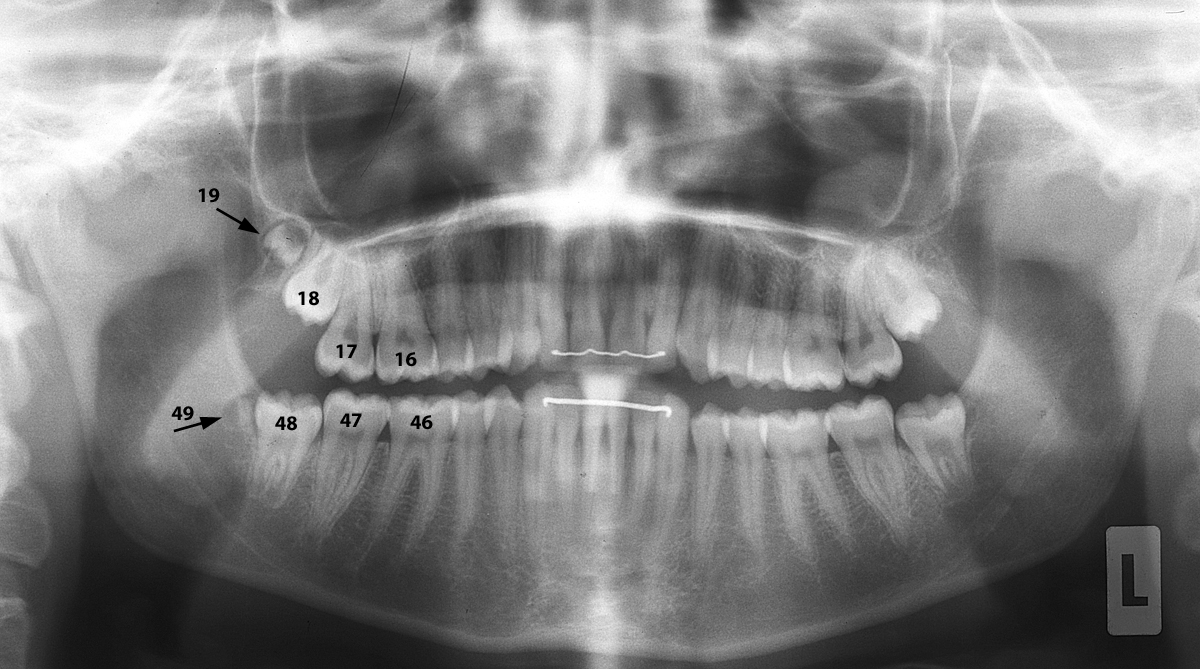

Überzählige Zähne im Seitenzahnbereich – «9er»

Anbei ein Fall eines 15-jährigen Mädchens, das auf der rechten Seite sogenannte «9er» hat (überzählige Zähne ganz «hinten», anschliessend an die Weisheitszähne).

Sie sind unten auf den Röntgenbildern dargestellt und markiert.

In der Regel werden solche überzähligen Zähne entfernt.

Dann und wann sieht man auch Fälle, in denen noch weitere Zähne vokommen (10er, …)